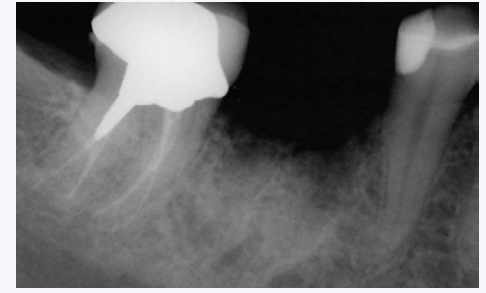

Bioopsy of bone core. Notice complete ridge reconstruction.

A full thickness mucoperiosteal flap was elevated and a trephine was used as the first bur for osteotomy preparation in the mandibular right first molar site (Figs. 7,8). A dental implant was inserted in dense bone which was fully stable at the time of placement. Histologic evaluation showed vital bone in the site (Fig. 9), which was allowed to heal for 3 months before uncovering (Fig. 10), prosthetic loading, and restoration.

In the presented case, vital bone was formed in the re-entered, regenerated site. In the mandibular molar site, 51% vital bone resulted with less than 1% remaining bone replacement graft material. This is in contrast to studies with bovine graft materials where 25-35% residual graft has been shown at all time periods (3). Additional studies are needed to compare vital bone formation in sockets grafted with this calcium sulfate mixture to other graft materials and the long-term dimensional stability of the bone regenerated.